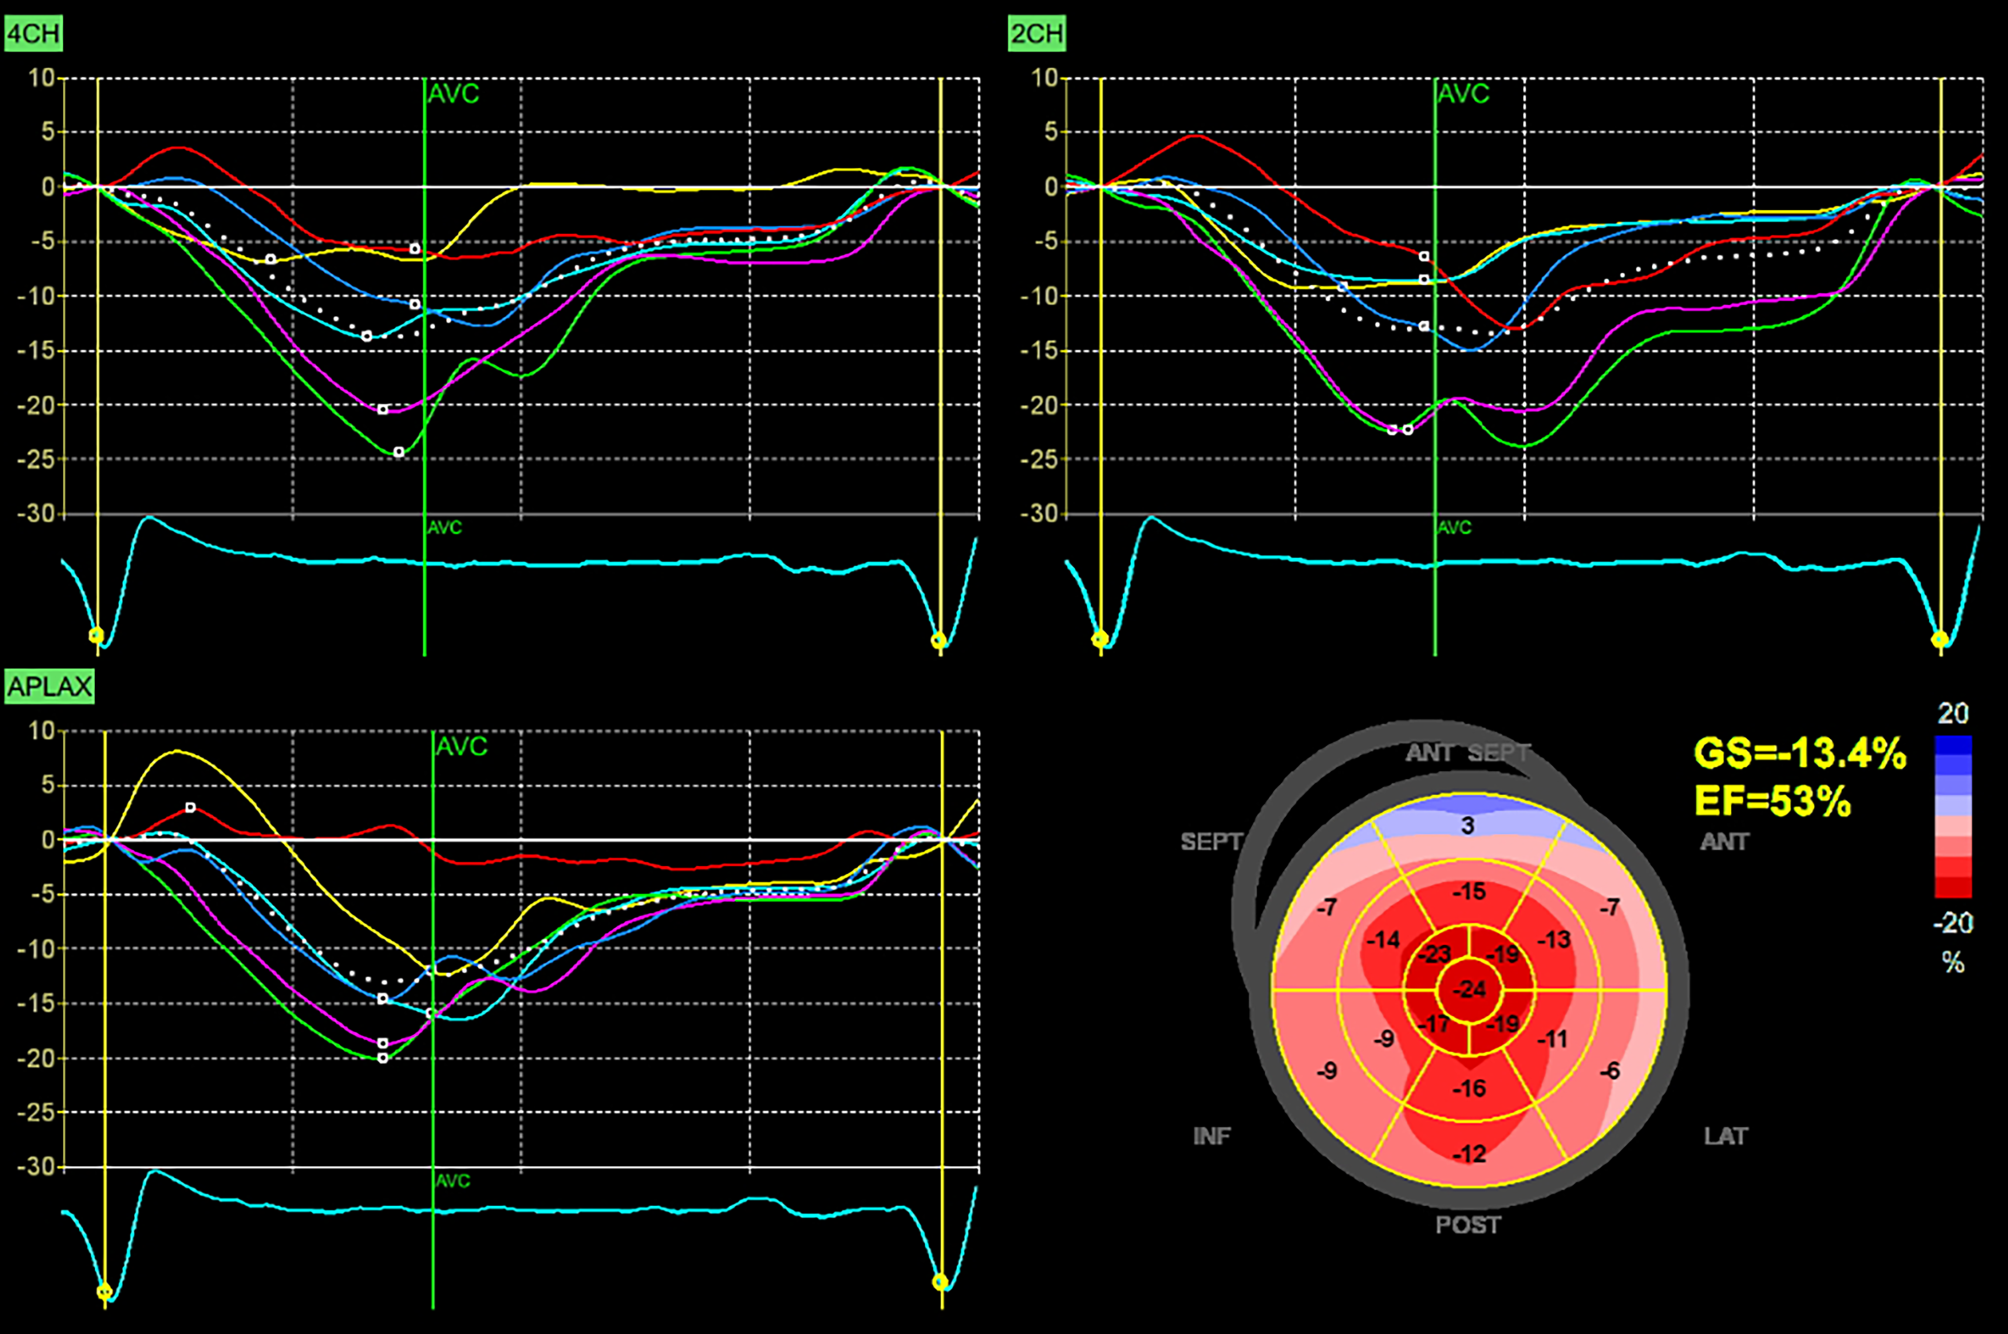

Fig. 2

Echocardiography: Two-dimensional strain analysis showing significant reduction of global longitudinal left ventricular strain together with the relative apical sparing pattern

During the first visit at our center in June 2023, the patient reported chronic shortness of breath consistent with functional class NYHA II, without any other symptoms of heart disease. His medications consisted of acetylsalicylic acid 100 mg once daily, clopidogrel 75 mg once daily, bisoprolol 5 mg daily, perindopril 5 mg daily and atorvastatin 20 mg daily. Blood pressure was 125/70 mm Hg, heart rate was 73 beats/min, respiratory rate was 16 respirations/min and oxygen saturation was 96% in room air. A holosystolic murmur at the left upper sternal border represented the main finding during the physical examination. Lung auscultation revealed clear breath sounds bilaterally. No signs of volume overload were present. An electrocardiogram (ECG) demonstrated sinus rhythm with first degree atrioventricular block and left anterior fascicular block. Laboratory tests did not reveal any significant abnormalities except for an elevation in NT-pro-BNP level (1137 ng/l) together with mild elevation of high-sensitive TnI level (51 ng/l). Echocardiographic examination confirmed the presence of pronounced concentric, diffuse LV wall thickening (septal thickness 17 mm, posterior wall thickness 15 mm, LV end-diastolic diameter 44 mm, relative wall thickness 0.68) with the absence of regional wall motion abnormalities and preserved LV ejection fraction of 71%, grade II diastolic dysfunction and left atrial dilatation. Global longitudinal strain was significantly reduced (−13.4%), with the relative apical sparing pattern (Fig. 2). Systolic anterior motion of the mitral valve leaflets was present causing significant dynamic LV outflow tract obstruction (LVOTO) with peak gradient of 70 mm Hg at rest (Fig. 3) and 140 mm Hg with a Valsalva manoeuvre. Due to this unexpected finding we decided to perform an endomyocardial biopsy for a definitive diagnosis of ATTR-CA. The biopsy revealed abundant extracellular amyloid deposits stained with Congo red. Subsequent immunohistochemical analysis demonstrated the presence of ATTR (Fig. 4). Additionally, myocyte hypertrophy and myocardial disarray were not present. The final diagnosis of cardiac ATTRwt1 was established after negative genetic testing excluding ATTRv. No pathogenic or likely pathogenic variant associated with sarcomeric HCM or Fabryʼs disease were found. Specific disease-modifying therapy with the transthyretin stabilizer tafamidis (61 mg per day) was initiated. Bisoprolol was increased up to 10 mg daily which led to resolution of the LVOTO and an improvement in functional capacity to NYHA class I.